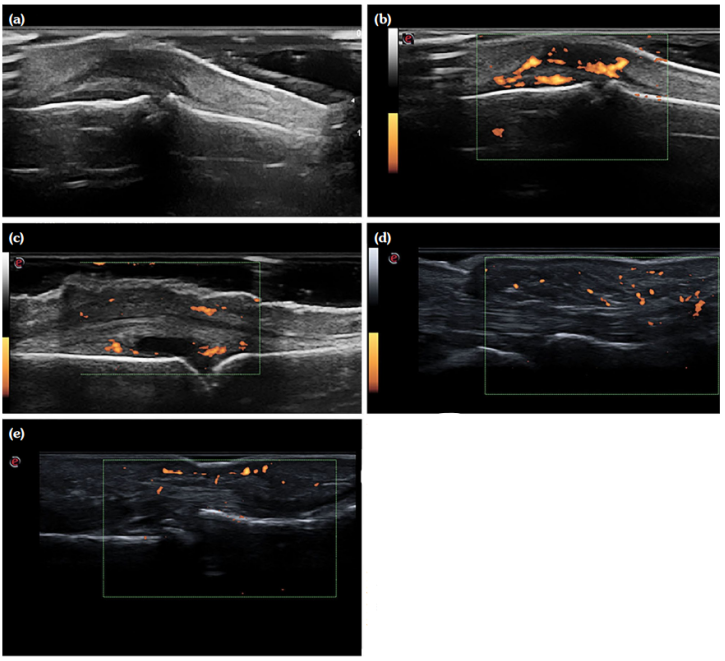

The palmar scan of the second MCP joint revealed a significantly higher incidence of tenosynovitis and pseudotenosynovitis in PsA patients (p<0.001), whereas the third MCP joint showed that pseudotenosynovits was significantly more prevalent in the PsA group (Table 2; Figure 1).